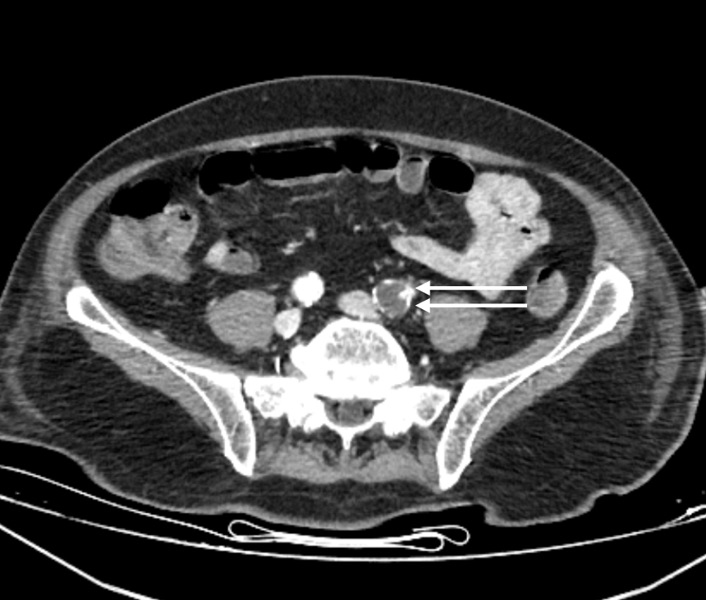

On the 13th day, the left foot was noted to be cold and ischemic, with the posterior tibial pulse not palpable. Similarly, the left hand was cold, and the radial pulse was absent. Arterial thrombosis was suspected, and Doppler ultrasonography confirmed thrombosis in the posterior tibial artery. A contrast-enhanced CT angiogram (Figure 1-3) revealed arterial thrombosis extending downward from the descending aorta, a splenic subcapsular ischemic appearance, arterial thrombosis narrowing the lumen in the left iliac and femoral arteries, and posterior tibial artery occlusion in the left leg. The patient was managed medically without surgical intervention, pentoxifylline 1500 mg/24 h infusion, dipyridamole 75 mg 1x1 tablet was started, and enoxaparin was increased to 60 mg twice daily.